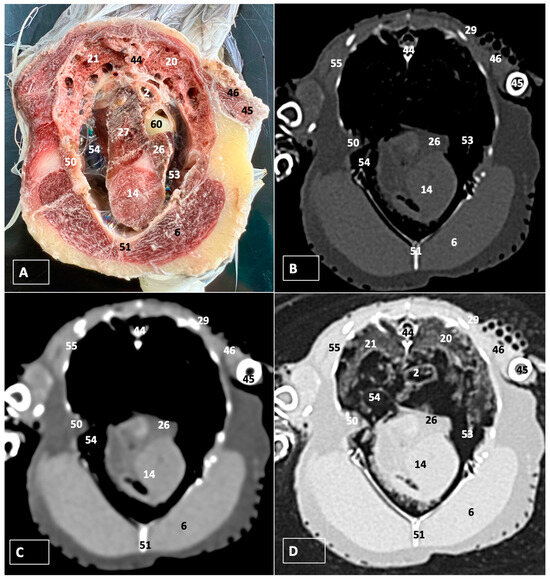

3. Results

3.1. Anatomical Dissections and Cross-Sections

3.2. Computed Tomography Images